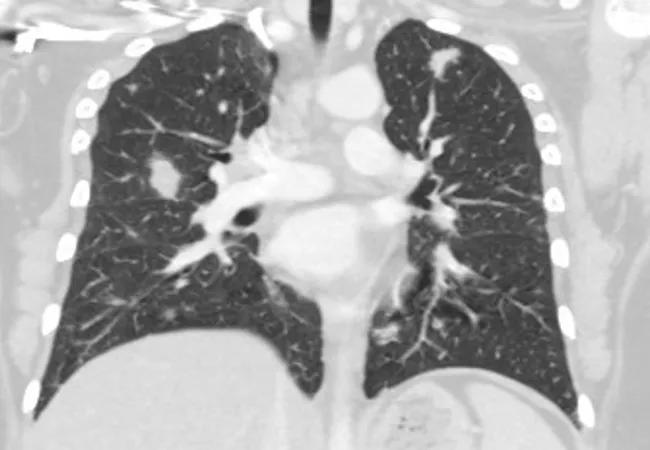

Pre-treatment. CT chest shows numerous bilateral upper lung and lower lung pulmonary nodules without cavitation or calcification, measuring up to 17 mm.

CT chest showing significant improvement in number and size of pulmonary nodules.